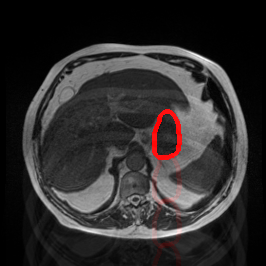

Bias Field Artifact

MRI GMAIMMbench Organ Recognition - Abdomen

Bias Field Artifact - L0 (Original)

L0

L0 (Original)

Bias Field Artifact - L1 (Moderate)

L1

L1 (Moderate)

Bias Field Artifact - L2 (Severe)

L2

L2 (Severe)

Question

Observe the MRI image. Can you identify the organ in the highlight area?

A fat B stomach C optic cup D gallbladder E optic disc

Ground Truth: B. stomach